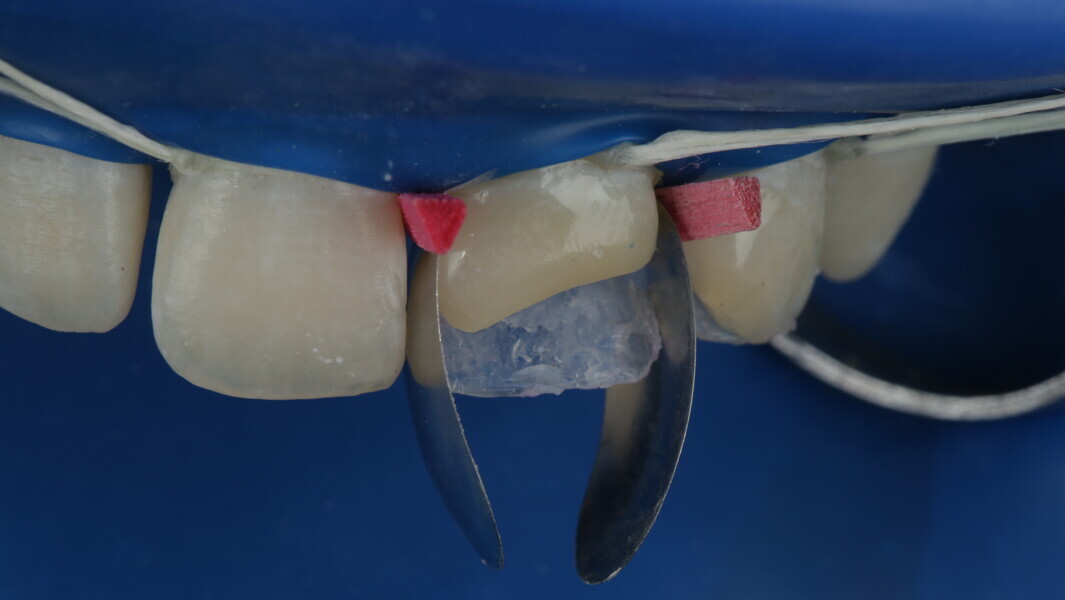

Fig 19-24: Contact build-up with band and wedge